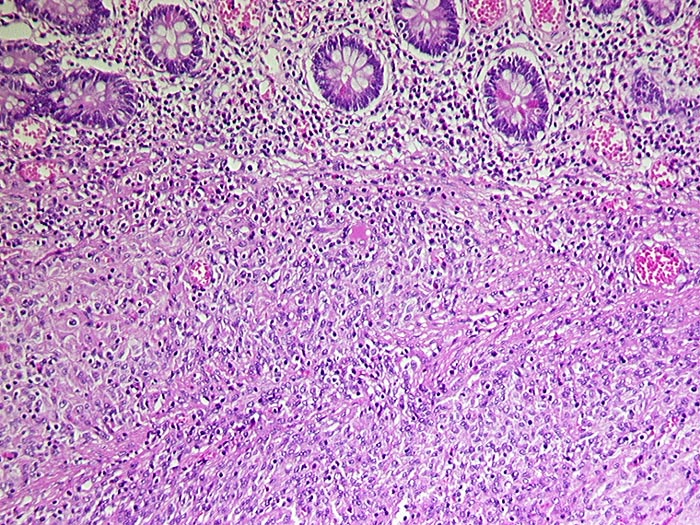

Gastrointestinaler Stromatumor (GIST)

maligner Tumor

Dünndarm

Spindelzelliger, von der Submukosa ausgehender Tumor. Die Mukosa wird vom Tumor nicht infiltriert.

Metastasen im mesenterialen Fettgewebe und in der Serosa. S-100 negativ, SM-Actin herdförmig positiv, CD 117 (c-kit) positiv.

Histologie